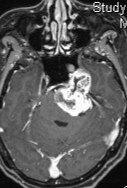

三叉神经鞘瘤(trigeminalneurinoma)的治疗选择-手术OR立体定向放疗/SABRtrigeminalneurinoma听神经瘤的治疗选择/桥脑一小脑角(CPA)综合征-手术or立体定向放疗听神经瘤(acoustictumor)的治疗选择-手术OR立体东西放疗OR随访观察立体定向中央放射消融(SCART)-iSABR-SRS-SABR-SBRT-TOMO放疗一、概述三叉神经鞘瘤占颅内肿瘤的0.2%~1%,在颅神经肿瘤中仅次于听神经瘤而居第二位。为良性肿瘤,常见于35~60岁,女性多发,男女比例为1:2。起源于三叉神经髓鞘的神经膜细胞,常见囊性变和出血坏死,有包膜,属脑外肿瘤。瘤体常发生于中颅窝岩骨尖部的三叉神经半月节,可沿一个或多个分支蔓延,也可发生于后颅窝三叉神经根上进人桥小脑角区。三叉神经鞘瘤中有50%源于三叉神经半月节,25%起于中颅窝三叉神经根神经节,属硬膜内肿瘤;另25%常见中、后颅窝,系硬膜内、外硬膜肿瘤。根据肿瘤的生长特点分为跨颅窝型、颅中窝型和颅后窝型。二、临床表现临床表现可归纳为三个主要方面,即三叉神经症状、邻近组织侵害症状及颅内高压症。(一)三叉神经症状为首发症状,发生率最高,早期主要表现为患侧颜面肉跳、面部及口腔麻木感、痛觉减退、及角膜反射迟钝或消失;其次为症状性三叉神经痛,咀嚼肌、颞肌萎缩。三叉神经眼支损害可有顽固性角膜炎。(二)邻近组织侵害症状取决于肿瘤的起始部位和发展方向。颅中窝型可因向内侵及海绵窦,向前侵及眶上裂而引起患侧突眼,外展及动眼神经麻痹、视力障碍等。压迫颞叶产生癫病、幻嗅。颅中窝型易破坏颅底形成颅内外沟通瘤。颅后窝型则多表现桥脑小脑角综合症,包括Ⅵ、Ⅶ、Ⅷ颅颅神经损害、锥体束征、小脑性共济失调及眼震。肿瘤向下发展可损害后组颅神经。哑铃型肿瘤可兼有前二型症状,但多以肿瘤首发或主体部位的症状为主。(三)颅内高压症肿瘤体积过大或压迫导水管、四脑室产生脑积水时可出现颅内压增高.三、辅助检查(一)颅脑CT表现颅中窝和颅后窝交界处卵圆形或哑铃形肿物,呈等密度或低密度。瘤体周围一般无脑水肿。相邻脑池和脑室可受压变形。题骨岩部尖端破坏。增强后实性者呈均一强化.囊性变者呈环状强化。骑跨颅中窝、颅后窝者呈哑铃状,为三叉神经鞘瘤特征性表现。CT典型图像如图1-6-9和图1-6-10所示。(二)MRI检查由于MRI具有多维成像和无颅骨伪影的特点,是诊断三叉神经鞘瘤重要的检查方法。MR表现;岩骨尖部或跨越中后颅窝的圆形、类圆形或哑铃状肿物、T1WI像为低或等信号。T2WI像为高或等信号,病灶周围一般无水肿,相邻脑池和脑室可受压变形。增强后多数明显均一强化,少数囊变者环形强化。MRI典型图像如图四、诊断与鉴别诊断(一)诊断本病根据临床表现及辅助检查多数可明确诊断。(二)鉴别诊断主要与脑膜瘤和听神经瘤相鉴别。1.桥小脑角区脑膜瘤:呈类形或半圆形,基底宽与岩骨相连,边缘清楚,囊性变较少,局部骨质为增生性改变,瘤体显著强化,可见“鼠尾征”。内听道往往不扩大。若脑膜瘤伴钙化,肿瘤边缘环绕不规则T2WI像高信号水肿区,结合局部骨质增生及脑膜增厚等表现诊断不难。2.听神经瘤:为桥脑小脑角区圆形或类圆形肿块,T1WI呈稍低或等信号,T2WI呈高信号,以内听道口为中心改变,内听道扩大,通常不跨越颅窝。五、治疗(一)手术治疗应尽早手术治疗,并应争取全切除。一期全切除困难者,亦应争取大部或次全切除,若情况允许,可行二期手术,以期根治。1.手术人路①后窝型宜采用一侧枕下桥小脑角入路。②颅中窝型及哑铃型与颅底结构关系密切,可侵及海绵窦、颈内动脉、眶部、岩骨甚更广泛的组织结构、且可形成颅底沟通瘤,因此应根据不同情况采取适宜的手术路径。③对于体积较大的肿瘤除应尽量采取颅底人路外,有时尚需采取联合入路,如哑铃型肿瘤在幕上、下部分均较大时,幕上下联合入路会提供更多的肿瘤全切除机会。④对于大的颅底沟通瘤,特别是颅内、外瘤体均较大时,单纯颅底或领面入路均会感到困难,宜采取经题下一耳前一题下窝人路,可提高全切除率,降低术后并发症。2.术中注意要点:可参照“岩斜区脑膜瘤”、“海绵窦脑膜瘤”等章节。3.手术前后典型图像如图1-6-15和图1-6-16所示。(二)放射治疗参见听神经瘤(三)药物治疗对肿瘤无效(×)。对症治疗可减轻三叉神经痛的症状

患者女性26岁,于2021年11月无明显诱因出现视物重影,主要为远处重影,未重视,2022年6月逐渐出现视物重影加重,同时伴有右侧肢体乏力,行走不利,间断出现耳鸣,休息可缓解,8月出现饮水呛咳,10月出现吞咽困难及头部胀痛,偶有恶心呕吐,就诊于威海卫医院行头颅核磁提示:右侧颅底内可见哑铃状团块影,边缘清楚,周围脑组织受压,中脑导水管受压,第三脑室稍扩张,中线居中,考虑神经源性肿瘤可能性大。患者及家属为进一步治疗来就诊。根据患者影像学检查及现病史,考虑右侧三叉神经鞘瘤可能性大,肿瘤体积大,周围组织明显受压,为避免病情进展脑疝形成,建议手术切除病变。入院后完善术前准备,择期行右侧慕上下开颅中、后颅窝占位性病变切除术➕侧脑室外引流术。术中分块切除肿瘤组织,手术顺利结束。术后患者神志清楚,精神好,面部感觉正常,眼球运动正常,四肢感觉运动正常。术后恢复好